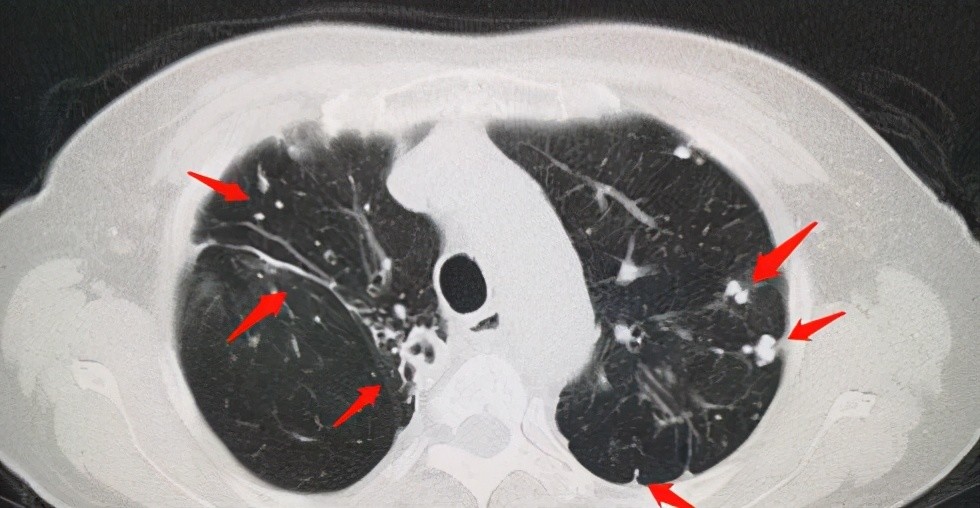

1.肺纹理增多

肺纹理增粗 , 或者肺纹理增重 , 是个影像学概念 , 多见于长期抽烟的人、老年人、肥胖的健康人 , 也可见于急慢性支气管炎者 。 如果没有任何症状 , 仅仅在体检报告中看到的单纯肺纹理增粗 , 其实没有什么实际的临床意义 , 可以认定为生理性肺纹理增粗 , 不需要去关注 , 也不需要处理 。 而如果近期有咳嗽 , 咳痰等症状 , 胸片报肺纹理增粗 , 医生可以认定为是气管炎、支气管炎 , 可以抗炎治疗 。